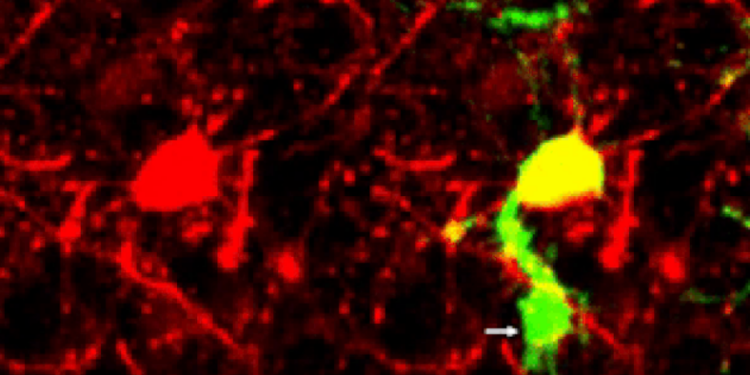

Команда сосредоточилась на глиальных клетках, ответственных за выполнение работы по очистке мозга; они использовали технику, названную 2Phatal, для воздействия на одну клетку мозга для апоптоза (гибели клеток) в мыши, а затем следовали по маршруту глиальных клеток с использованием флуоресцентных маркеров.

Исследователи наблюдали, как одна микроглия охватывает тело нейрона и его основные ветви (дендриты), в то время как астроциты предназначались для удаления меньших соединительных дендритов. Они подозревают, что NG2 может помочь предотвратить распространение мертвых клеток.